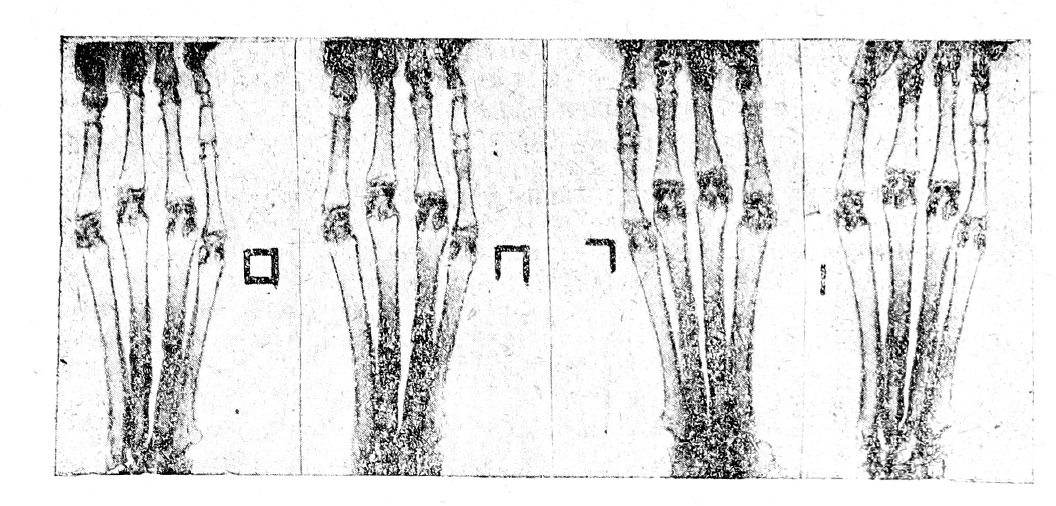

При анализе этих цифр опытов №№ 19,20, 21, 22 и 30 мы видим, что под влиянием подкожного введения эмульсии № 1 на 10-й день получены колебания уровня Са в крови от 1,0 до 2,6 млгр. %; на 20 й день от 1,2 до 2,0 млгр.% и на 30-й день от 1,6 до 3,0 млгр-. %. Наиболее высокие цифры колебания Са дал кролик № 22, у которого получен исключительно прекрасный клинический результат: у него полное сращение сломанных костей произошло в 15 дней вместо нормального среднего срока в 30 дней. Могучее действие эмульсии № 1 в этом опыте под- подтверждается четырьмя рентгенограммами, произведенными в установленный срок—на 15, 20, 25 и 30-й дни от начала опыта (рис. №№ 5-8). Из рентгенограмм мы видим, что уже на 15-й день имеется ясная тень от костной мозоли, на последующих снимках наблюдается быстрое дальнейшее формирование костной мозоли с прекрасной ее оссификацией. Такой результат получен несмотря на то, что отрезки сломанных костей стоят по отношению друг к другу неправильно, а именно—они налегают друг на друга и смещены в сторону, что хорошо заметно на рентгенограммах, произведенных на 20 и 30-й дни.

Рис. 5—8. Сращение перелома под влиянием подкожного впрыскивания костной эмульсии № 1.

Сращение полное произошло на 15 день. Опыт № 22.

Надо отметить, что наибольшее повышение Са получено в опыте № 42, где на 30-й день оно достигло 3,0 млгр. %. В этом опыте констатировано полное сращение перелома на 20-й день с образованием прекрасной костной мозоли и с быстрой ее дальнейшей оссификацией, что наглядно можно проследить по прилагаемым рентгенограммам (рис. №№ 9—12). Этот случай надо считать особенно показательным в том отношении, что на рентгенограмме, полученной на 30-й день, уже начинается процесс обратного развития костной мозоли и формирования костно-мозговой полости на месте перелома. В опыте № 60 также развилась пре красная костная мозоль и полное сращение получено на 25-й день несмотря на некоторое смещение отрезков сломанных костей.

Рис. 9 — 12. Сращение перелома под влиянием подкожного впрыскивания костной эмульсии № 11.

Полное сращение произошло на 20-й день. Опыт № 42.

(Знаки сбоку указывают дни, в которые производились рентгенограммы | = 15 день; [_=20 день; [_| = 25 день; □ = 30 день).